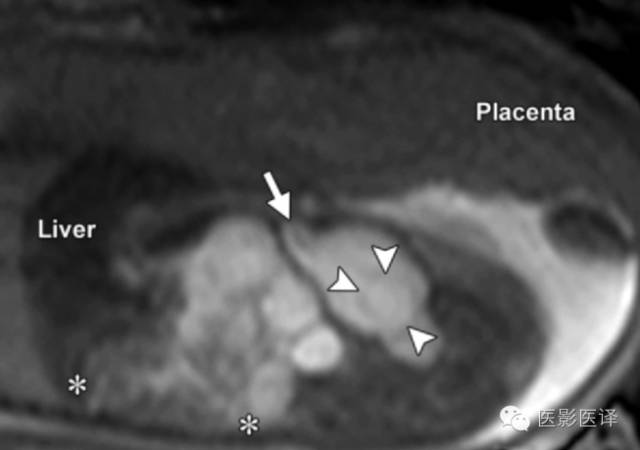

图11.输尿管囊肿及输尿管积水。(a)通过胎儿盆腔的超声斜横断面图像显示膀胱(B)内由输尿管囊肿(Ur)引起的“膀胱内膀胱”的征象。关注由此引起的输尿管积水(箭)。箭头指示脐动脉绕过膀胱,(b)同一胎儿,通过右肾的超声冠状面图像显示明显的肾盏扩张(箭)和被阻塞的上半部分肾皮质变薄。

脐尿管囊肿或残留

阴道积液

图14.晚孕期胎儿的子宫阴道积液。B=膀胱,U=子宫。(a)超声矢状位图像显示阴道梗阻扩张充满积液,与扩张的子宫通过宫颈相通(箭)。膀胱位于阴道前方,扫描过程中大小和形态会发生变化。(b)MRI T2WI序列矢状位的中线图像显示扩张的阴道延伸至会阴部。子宫向上移位,位于肝下缘胆囊后方(GB)。膀胱受压向前移位。箭=脐带插入位点。